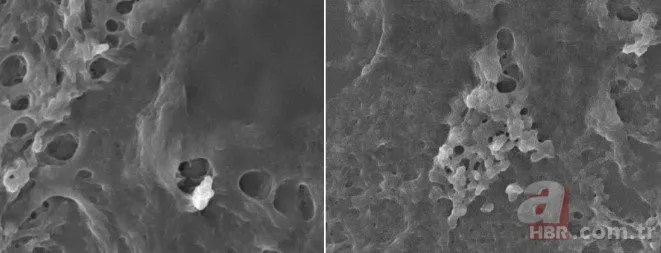

Bilim insanları, taramalı elektron mikroskobu (SEM) ve enerji dağılımlı X-ışını spektrometrisi (EDS) ile yaptıkları incelemelerde, beyindeki partiküllerin karbon bazlı olduğunu doğruladı.

Karaciğer ve böbrekteki MNP bileşen miktarının benzer oranlarda olduğunu saptayan araştırmacılar, beyindeki plastiklerin "mikroskobik boyutlarda cam kırığı" şeklinde gözlemlendiğini belirtti.